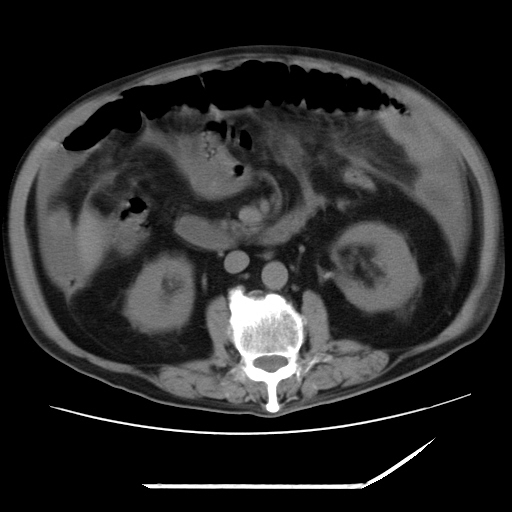

以下是引用zxl51642在2009-8-12 18:55:00的发言:[br]1、肠系膜脂肪浑浊,密度增高,腹水,支持腹膜炎诊断;2、右肾盂及输尿管中段结石,左输尿管起始段结石;3、胆囊切除术后改变?4、双侧胸膜腔少量积液;5、胰腺体积不大,勾勒清楚,肾前筋膜无增厚,不支持胰腺炎,请结合血尿淀粉酶及临床。